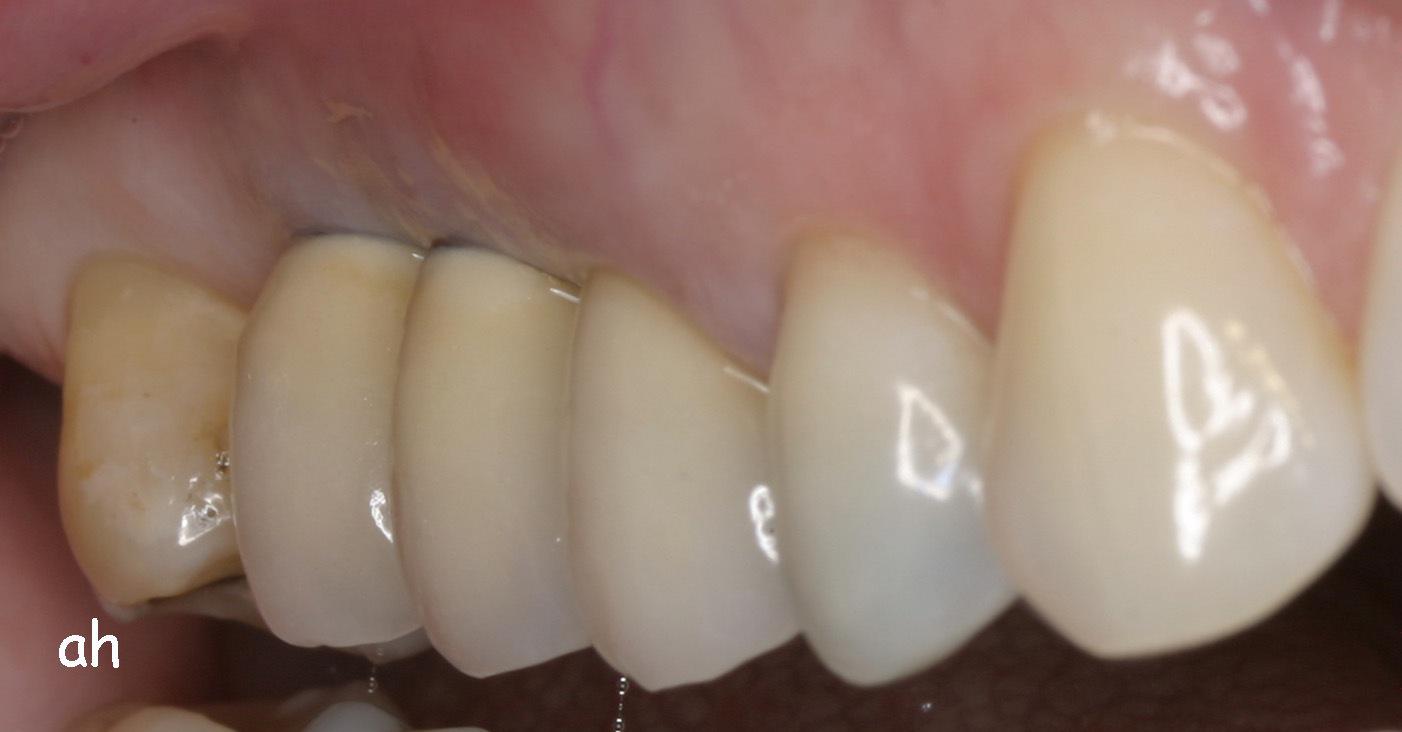

Exemple 3: Puis sur ce moignon, la couronne en céramique est scellée.

Exemple3: La couronne en place.